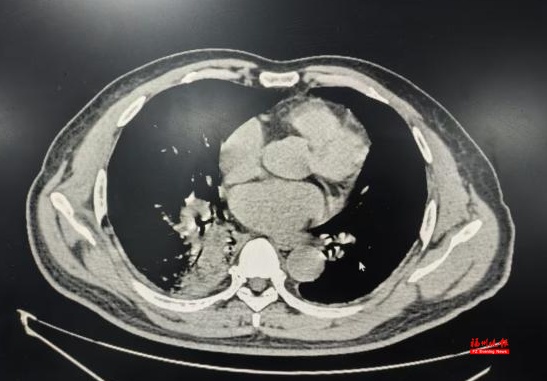

“会不会是鼠咬热?”林秀华心里打了个问号。但结合患者的肺部CT显示右下肺炎症,以及长期接触家禽的经历,她怀疑可能另有“真凶”。

最终确诊为鹦鹉热衣原体肺炎

吴先生住院期间就先后出现了肝损伤、肺炎加重。“幸好诊断明确后立即调整了治疗方案,两周后,吴先生病情渐渐好转了。”林秀华主任介绍,鹦鹉热如果诊断及时、治疗规范,预后一般良好;但如果延误治疗,病死率可达15%~20%。